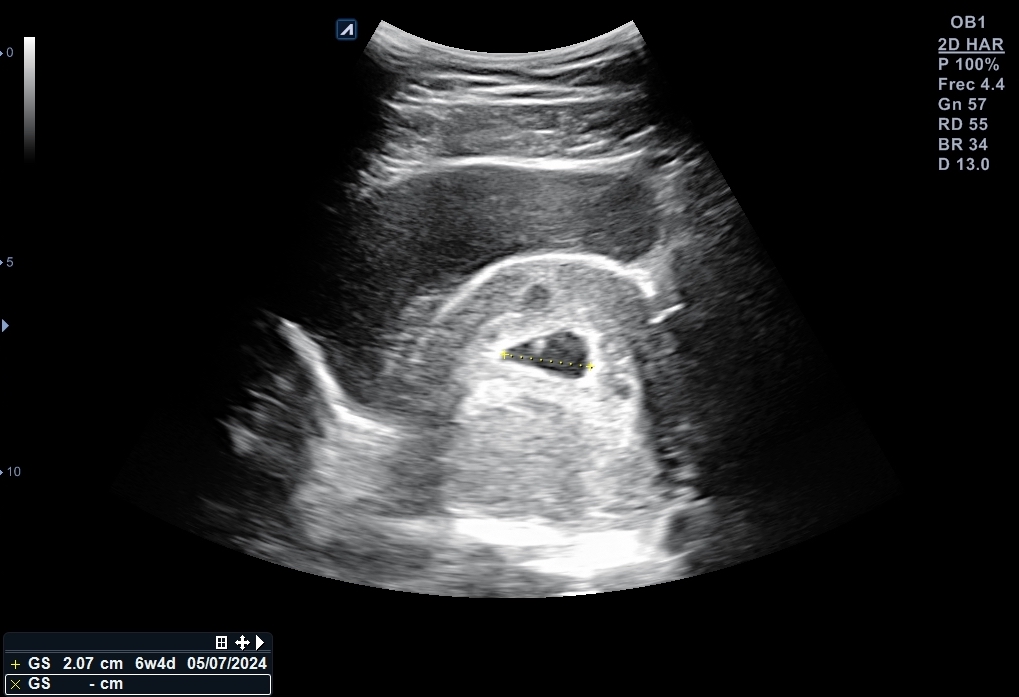

Se explora pelvis con sonda cónvex: vejiga distendida de paredes lisas y homogéneas. Útero en anteversión con endometrio decidualizado y saco embrionario en su interior, bien posicionado con una estimación de 6 + 2 semanas de gestación. Se localiza cuerpo lúteo en anejo izquierdo que, además está aumentado de tamaño.

Nueva ecografía: saco embrionario con embrión con latido fetal a 135 lpm y se data de 6 + 4 semanas. Se cita para analítica de primer trimestre, así como con Obstetricia.